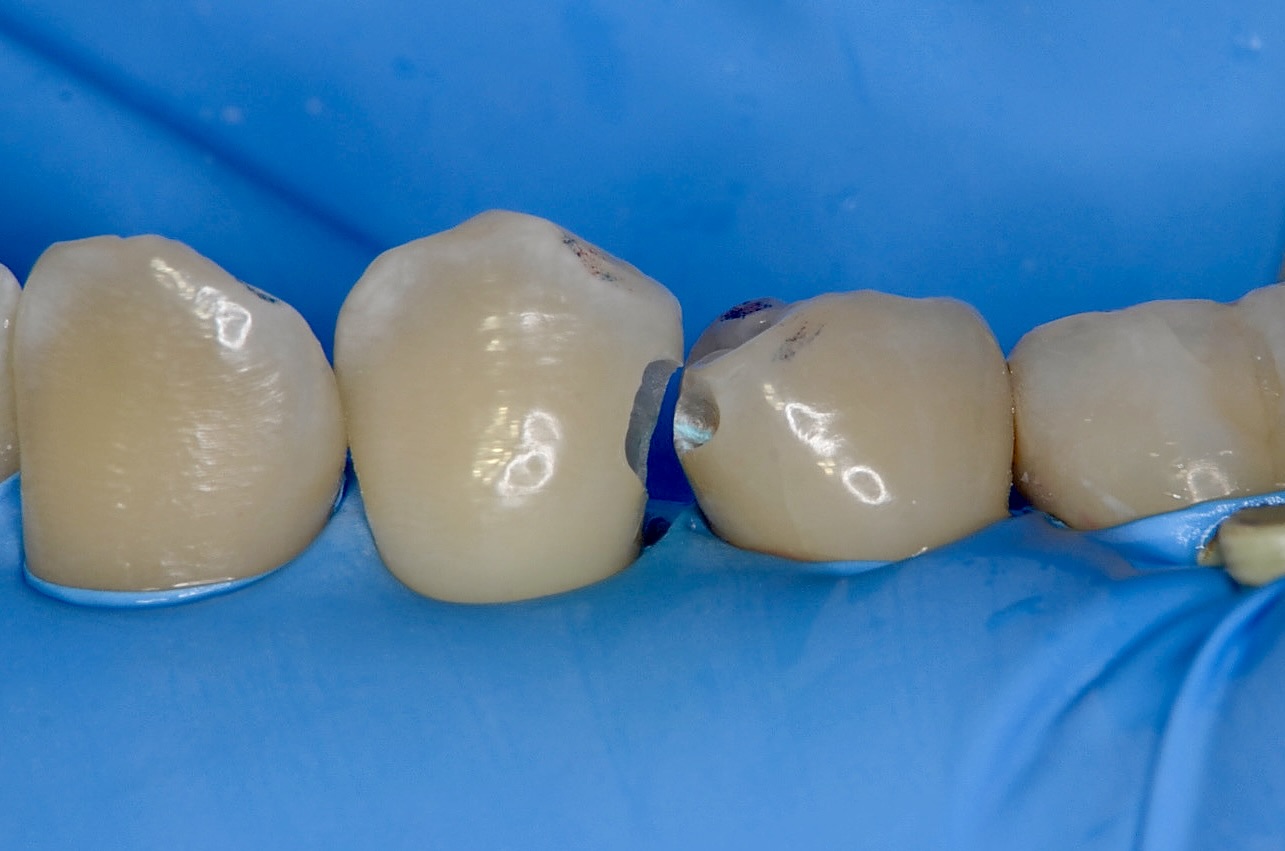

噛み合わせの確認

歯の角の部分を残す方が、歯の強度を保てます。 どこを削ってどこを削らないか?咬合紙という色をつける紙を噛んでもらって歯に色をつけます。色がついている部分をできるだけ避けて削ります。 -

舌側から見る

良く見ると4番は歯並びが少し乱れ、3番の遠心の下に食い込んでいます。 -

4番近心

3番遠心部を削ってるが故に4番の近心部のアプローチがしやすくなりました。 -

3番虫歯除去

完全に虫歯を取り切りました。こんなに虫歯が広がっていたことがわかります。 -

4番虫歯除去